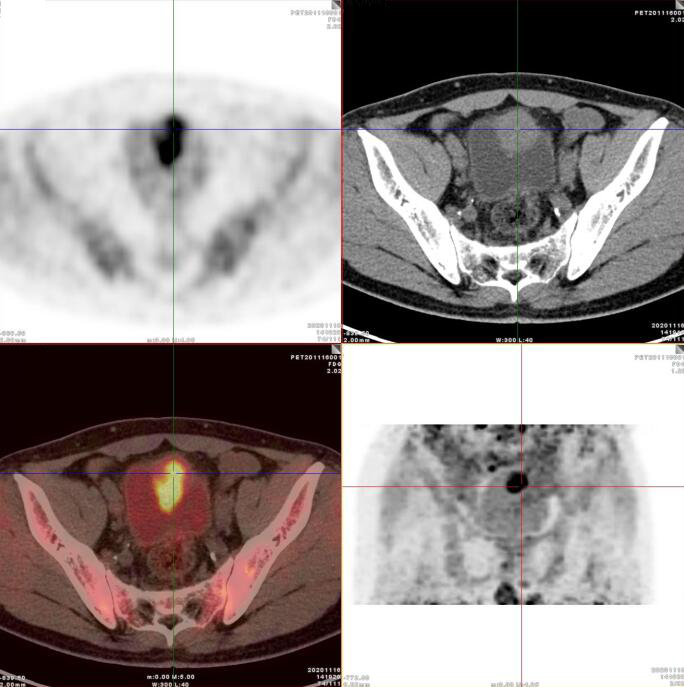

臍尿管擴(kuò)張,其管壁不均勻增厚,相應(yīng)區(qū)域膀胱頂前壁見一軟組織密度塊影,呈縱向生長,形態(tài)不規(guī)則,大小約3.3x3.8x6.3cm,內(nèi)見斑點(diǎn)鈣化!

膀胱頂前壁軟組織腫塊,放射性攝取SUV Max4.5

膀胱頂前壁軟組織腫塊,放射性攝取SUV Max4.5,延時(shí)4小時(shí)SUV Max8.3

臍尿管區(qū)及膀胱頂前壁軟組織腫塊,代謝增高,考慮臍尿管惡性腫瘤(臍尿管癌),建議穿刺活檢。